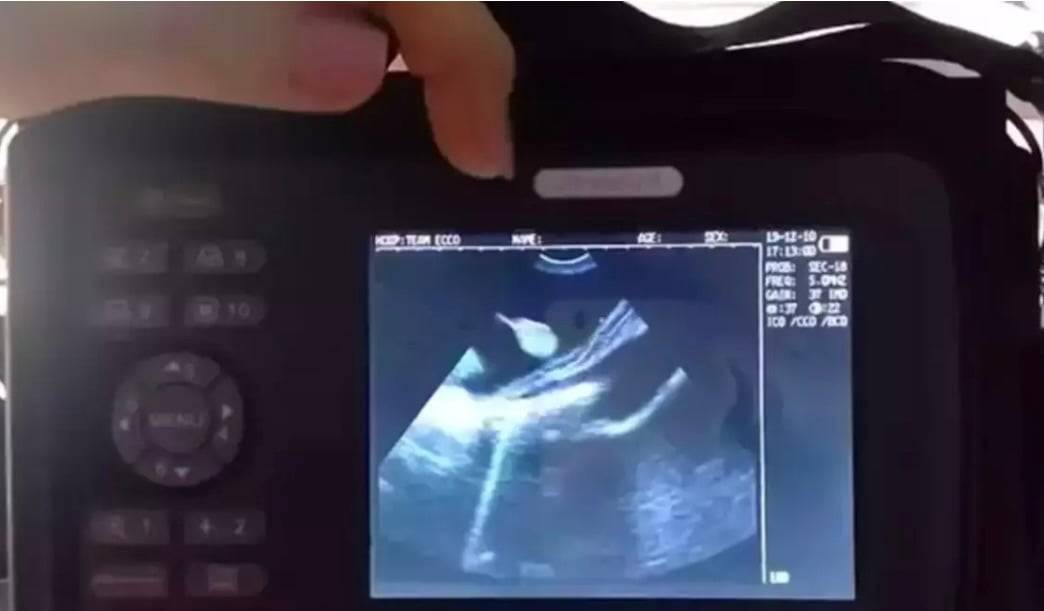

Employees on the aquarium carried out an ultrasound on the stingray and found that she was pregnant with 4 pups.

Check out this: